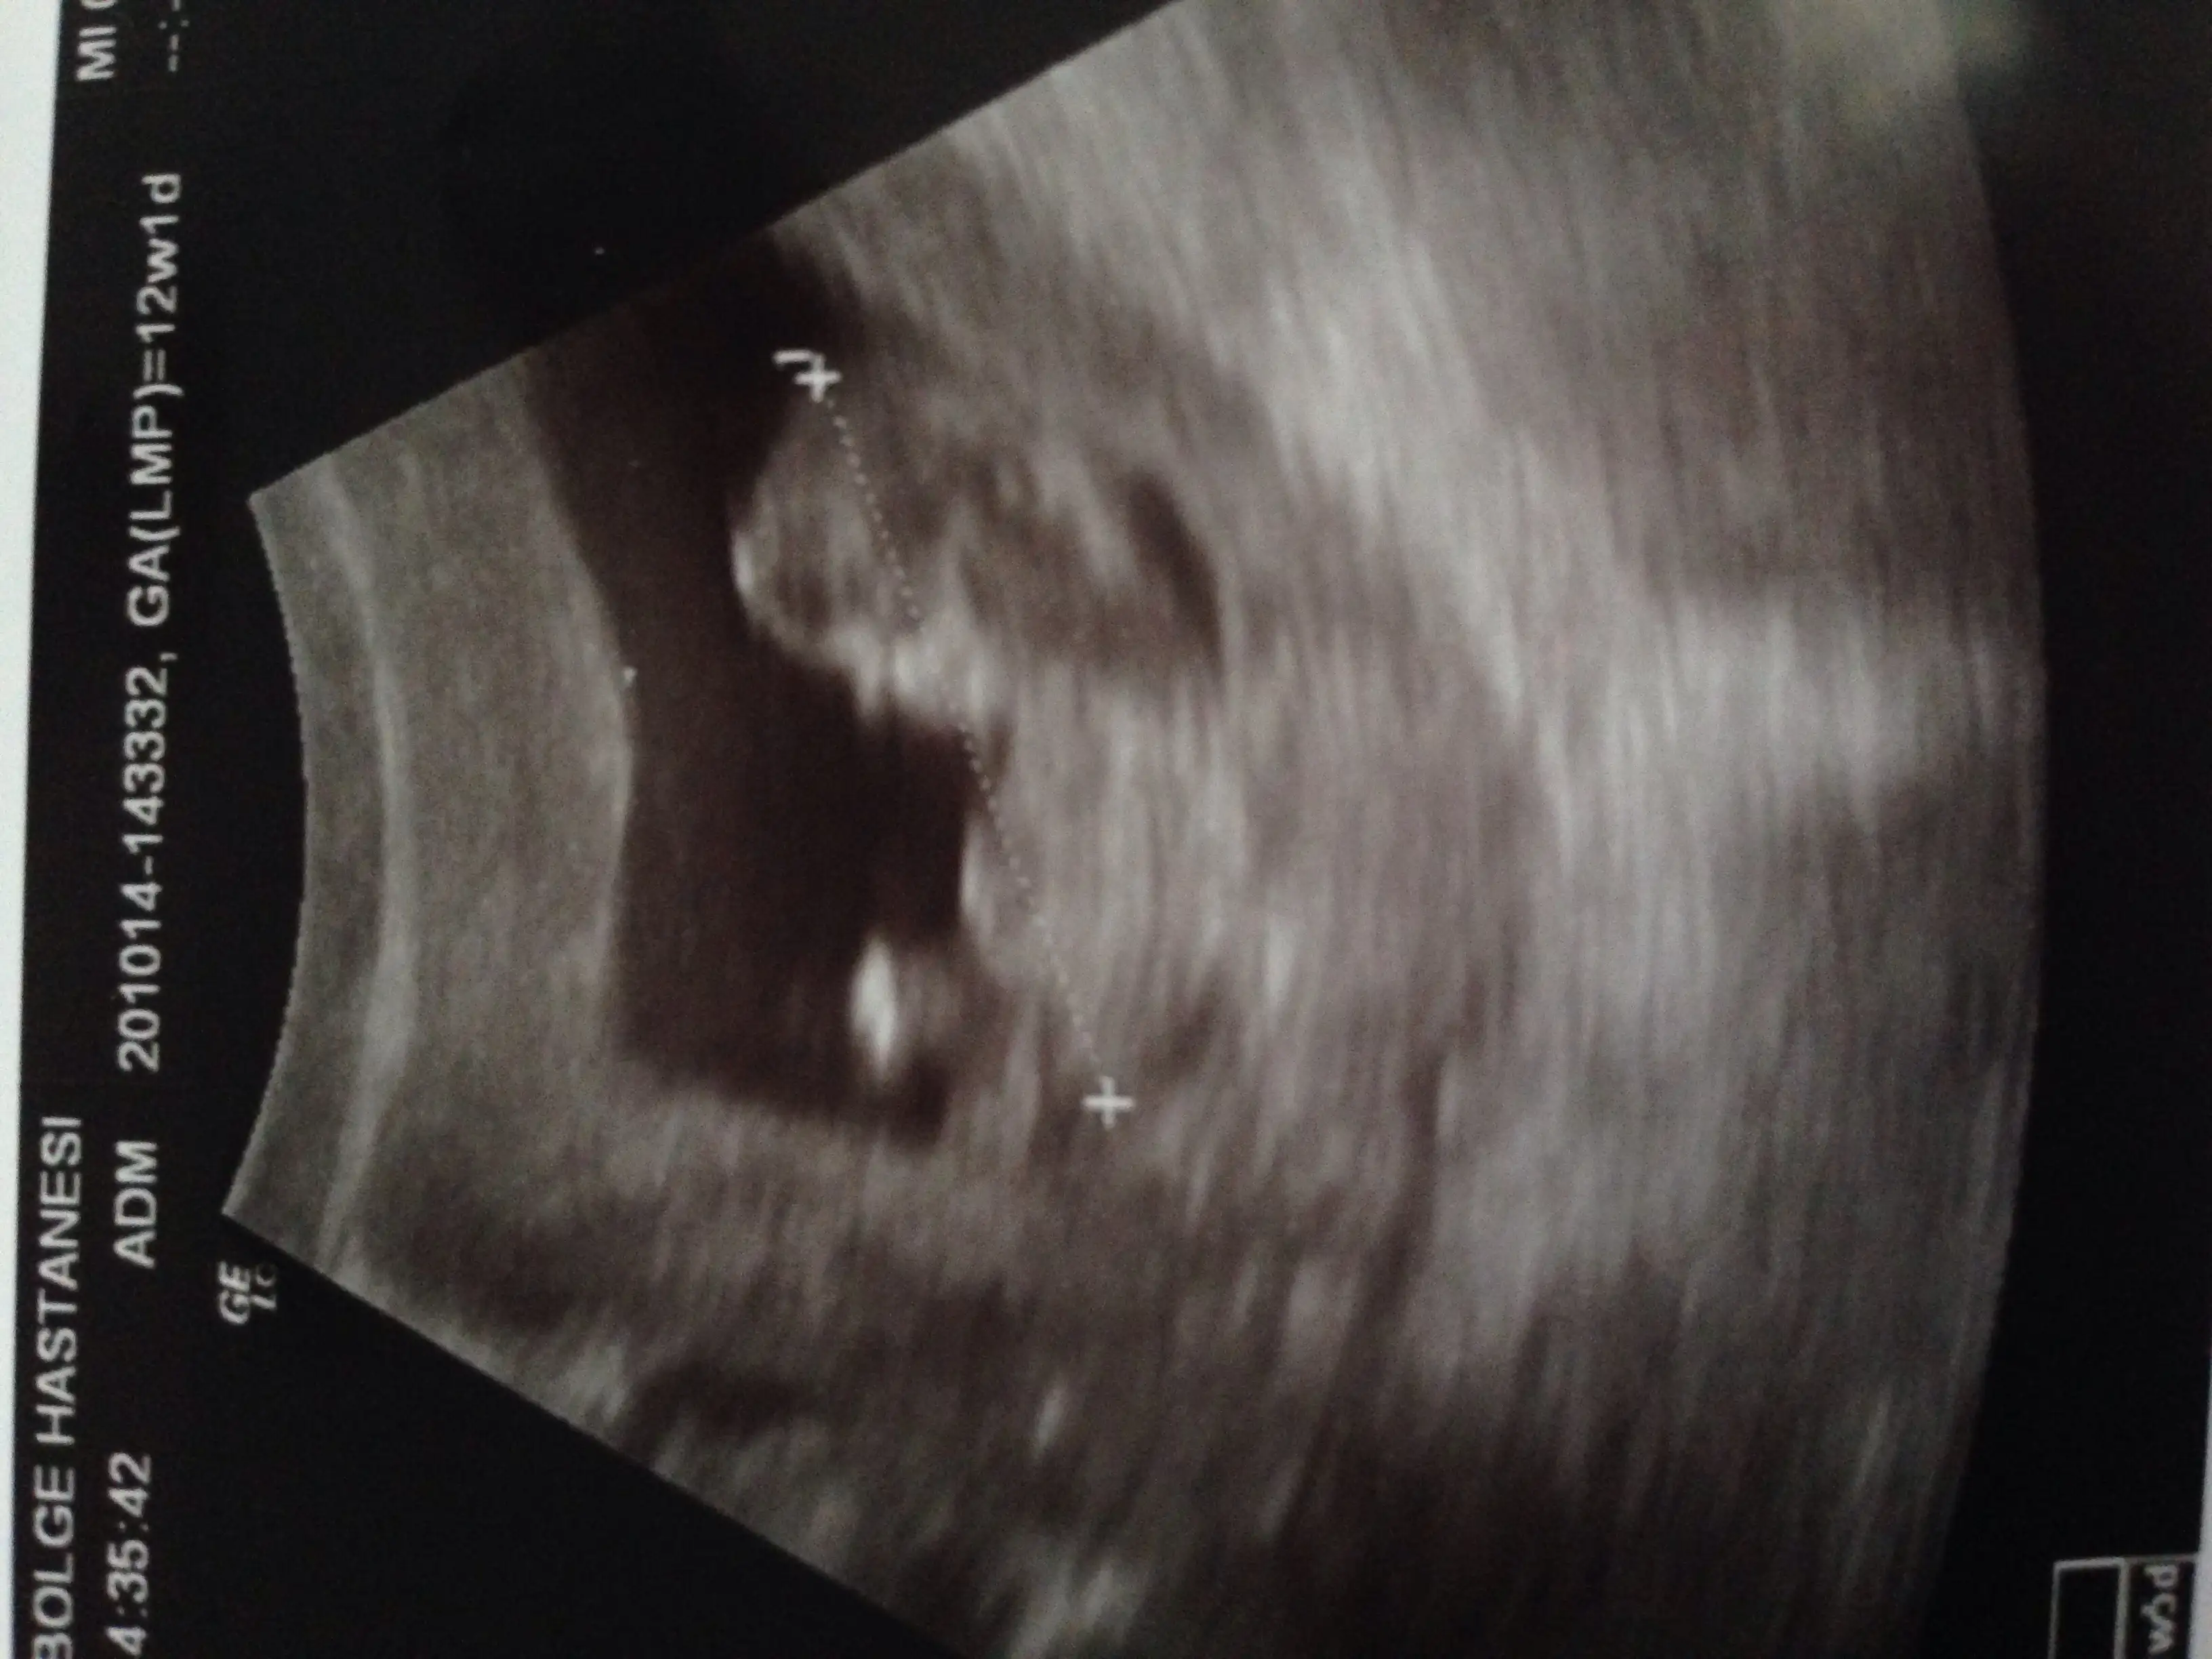

Kızlarrrrr merhabalar hepinize randevum vardı ikili test için. Doktora çikolata yiyip gittim ilk defa ve çok mutluyum kızlar. Poposunun üstünde zıp zıp zıplayan kollarını ayaklarını oynatan bir bebiş gördüm :) yerinde balerin gibi dönüyordu harikaydı :) hiç durmadı yerinde çok güzeldi kızlar. Ve bende son zamanlarda hiçbişey hissetmiyordum. Bişey oldu diye korkuyordum. Çünkü belirtilerim hiç yok nerdeyse. Korkmayın yani bebişler çok iyi :)

Bu arda doktorum askında ikili test işin çağırmıştı. Ama bugün vazgeçti bence gelişimini görünce. Ya da ben ona yordum, çünkü kesin yapıcaz demişti ama bebişi görünce açıkladı istiyor musun ikili testi. Bu sadece bir olasılık. Kesinliği yok. Sonuç riskli çıkarsa karından su alınıyor diye. Bende siz ne düşünüyorsunuz dedim. Burun keniği çıkmış ense kalınlığı iyi gelişimi haftasıyla uyumla kol ve bacak gelişimi çok iyi dedi, bence gerek yok aldırmayacaksan dedi. Yine de sen bilirsin tabi senin kararın dedi. Bende gerek yok ozaman dedim. İçim de çok rahat bebişim her şekilde kabulüm :)

Boyu baştan popoya 5cm olmş kızlar valla süt için bol bol. 11+5 teymişim hala 2 gün geri sanırım :) bir ay sonraya randevu verdi.

Gelelim cinsiyete bence biraz anladı ama söylemedi kızlar 16. Haftada konuşuruz dedi. Şuan çok erken dedi. Tahmin etseniz falan diye geveledim ama cık :) yani yine öğrenemedik :) bu da usg si kızlar :)